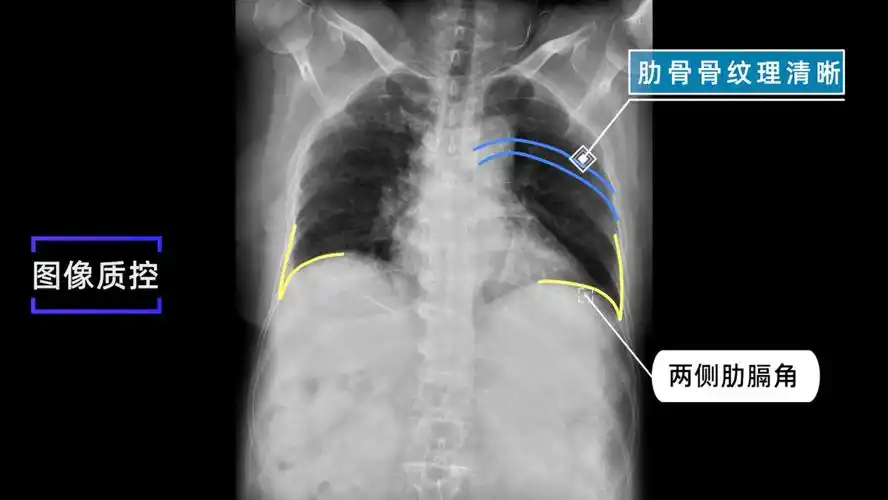

1 x线检查方法(2学时)定稿ppt

x线规范化检查胸部正侧位摄影视频及图文详解

x线规范化检查膈上下肋骨摄影视频及图文详解